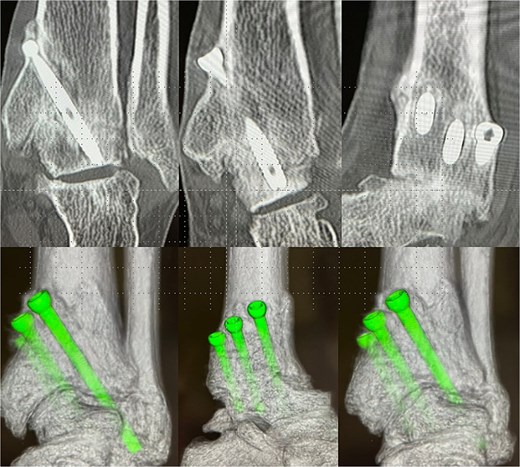

For the first four weeks, the patient remained non-weight-bearing in a below-knee cast, performing only toe range-of-motion exercises. Partial weight-bearing was initiated at week 5 and advanced weekly to full weight-bearing by week 8. An ankle-supporting walking boot was used until bone union was confirmed radiographically and by CT at 12 weeks (Fig. 4). At six months postoperatively, she returned to full professional wrestling matches while wearing customized rigid high-cut boots for joint protection.

Postoperative-6 months radiological imaging: CT finding. The tibiotalar joint has achieved bony union, and the articular surfaces are anatomically reduced with a horizontal alignment.

At 1.5 years, hardware removal was performed, with imaging confirming solid osseous union (Fig. 5). The Japanese Orthopaedic Association (JOA) score improved from 56.0 preoperatively to 81.4 at one year and 84.7 at the final 6.5-year follow-up. She resumed 60–70 matches per year without ankle pain, swelling, or motion-related discomfort. Her retirement after 6.5 years was unrelated to the ankle, resulting instead from cervical spine trauma and bilateral knee degeneration. Throughout follow-up, she remained free of ankle-related complications or functional restrictions.

Plain radiograph after hardware removal. At 1.5 years after surgery, the patient underwent hardware removal. Although the osteoarthritic changes in the subtalar joint have slightly progressed, radiographic evaluation confirmed solid osseous union at the tibiotalar joint.